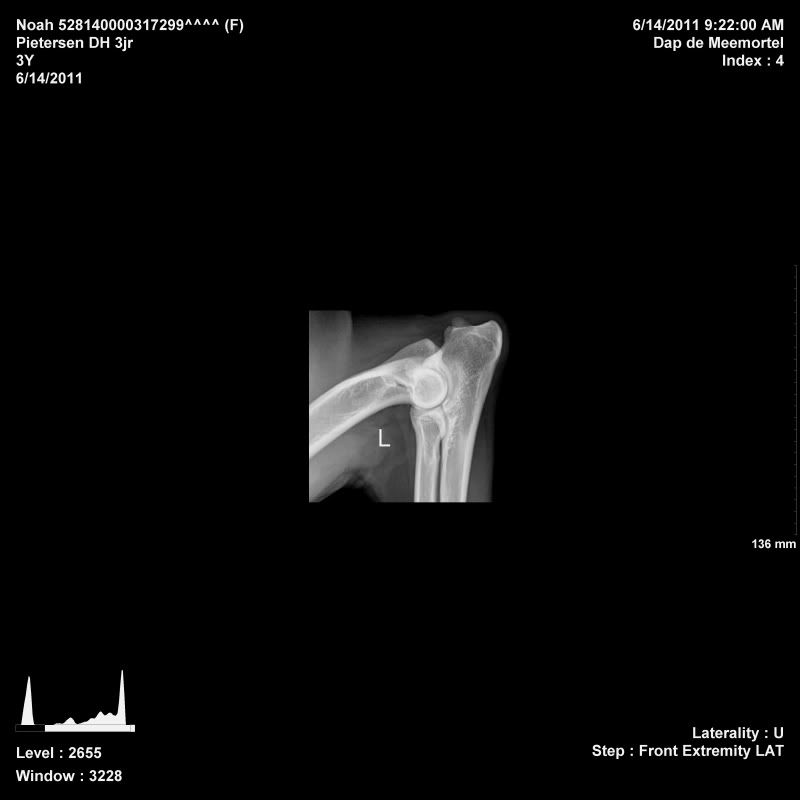

Noah is toen ze 11 maanden gerontged op ellebogen en heupen, dat was toen helemaal goed. Daarna 2 jaar fanatiek gaan sporten (1x in de week flyball, 2x in de week ipo). Voor mijzelf wilde ik graag weten wat 2 jaar sporten voor invloed heeft op de gewrichten, zodoende ben ik vandaag wezen rontgen in Budel. Ze is ook meteen gecastreerd, zodat ze maar 1x onder narcose moest

Haar heupen, ellebogen en rug waren wederom perfect! De DA was te spreken over haar gewrichten

Afbeelding